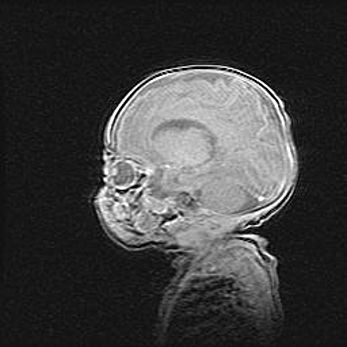

Неполная лизэнцефалия (пахигирия). Открытая гидроцефалия.

Возраст: 17 дней

Вес: 3110 г

Пол: мужской

Окружность головы: 33,5 см

Срок гестации: 35-36 недель

Лизэнцефалия—недоразвитие корковой пластинки и мозговых извилин в результате нарушения миграции нейронов коры. Поверхность мозговых полушарий гладкая. Микроскопически выявляется отсутствие нормальных слоев коры и скопление групп нейронов в подкорковом белом веществе.

Пахигирия—уменьшение числа вторичных извилин. В пораженном полушарии нервные клетки образуют толстый недифференцированный слой с неправильно расположенными нервными волокнами и группами гетеротопных клеток. Нервные клетки незрелые. Белое вещество истончено. При этом нередко аномально развит корково-спинномозговой путь.